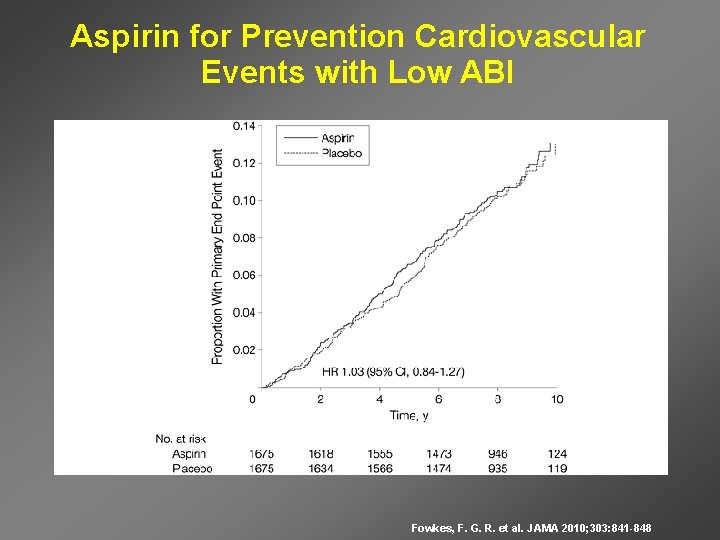

Aspirin for Prevention Cardiovascular Events with Low ABI Fowkes, F. G. R. et al. JAMA 2010; 303: 841 -848